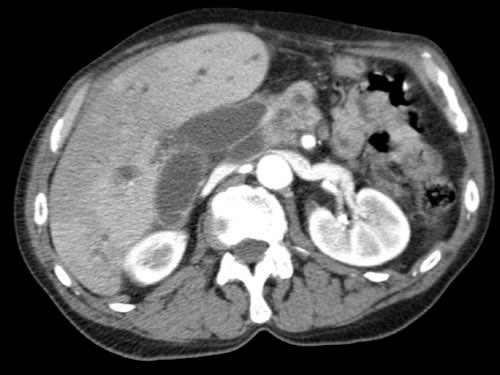

Các hình ảnh mặt phẳng đứng ngang của một bệnh nhân có khối u ở đầu tụy và động mạch gan phải phụ thêm.

Lưu ý sự áp sát của động mạch phụ thêm bởi khối u.

Các hình ảnh cho thấy một biến thể giải phẫu trong đó động mạch gan chung xuất phát hoàn toàn từ SMA.

Động mạch gan được thấy đi trong nhu mô đầu tụy (mũi tên vàng và xanh lá trong B).